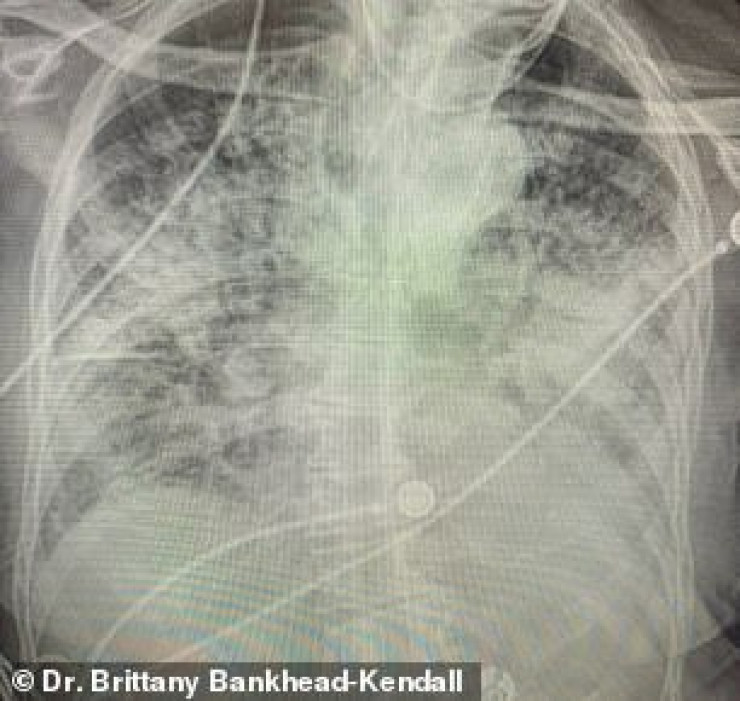

По словам хирурга, легкие выздоровевших пациентов с COVID-19 выглядят намного хуже, чем у курильщиков. Снимок выглядел почти полностью белым. Врач пояснила, что помутнение легких обычно указывает на то, что они наполнены такими веществами, как жидкость или бактерии, а также плотными рубцами и повреждениями.

"Легкие после коронавируса выглядят хуже, чем любые ужасные легкие курильщика, которые мы когда-либо видели. И они разрушаются", - заявила она.

По ее словам, многие эксперты в области здравоохранения концентрируют внимание на показателях смертности, а не на долгосрочных последствиях выживших. Доктор Бэнкхед-Кендалл также отметила, что почти у всех пациентов из тех, кого она лечила, и тех, кто переболел коронавирусом, был плохой рентген грудной клетки.

Врач добавила, что коронавирус часто приводит к таким осложнениям, как пневмония, которая возникает при наполнении легких жидкостью. Поскольку воздушные мешочки наполняются жидкостью, они не могут принимать достаточно кислорода и воспаляются, что приводит к таким симптомам, как кашель и одышка. Она подчеркнула, что если человек все еще испытывает одышку после выздоровления от COVID-19, то ему стоит немедленно обратиться к врачу первичной медицинской помощи.